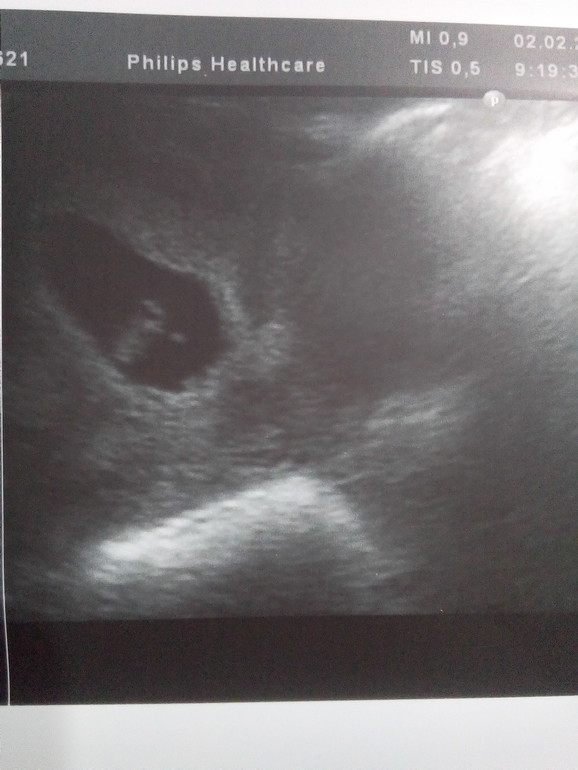

В 7+4( по животу):

ПЯ 30мм, КТР 15 мм, ЧСС 164 уд/ мин, ЖМ 5 мм, плацента в дне матки.